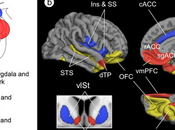

The Amygdala as the Hub of Three Brain Networks Supporting Our Social Life.

I pass on this very useful summary by Bickart et al. that summarizes brain connectivity experiments in rodents, monkeys, and humans to develop a description tha... Read more